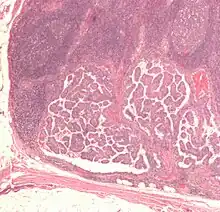

The cells in a metastatic tumor resemble those in the primary tumor. Once the cancerous tissue is examined under a microscope to determine the cell type, a doctor can usually tell whether that type of cell is normally found in the part of the body from which the tissue sample was taken.

For instance, breast cancer cells look the same whether they are found in the breast or have spread to another part of the body. So, if a tissue sample taken from a tumor in the lung contains cells that look like breast cells, the doctor determines that the lung tumor is a secondary tumor. Still, the determination of the primary tumor can often be very difficult, and the pathologist may have to use several adjuvant techniques, such as immunohistochemistry, FISH (fluorescent in situ hybridization), and others. Despite the use of techniques, in some cases the primary tumor remains unidentified.

Metastatic cancers may be found at the same time as the primary tumor, or months or years later. When a second tumor is found in a patient that has been treated for cancer in the past, it is more often a metastasis than another primary tumor.